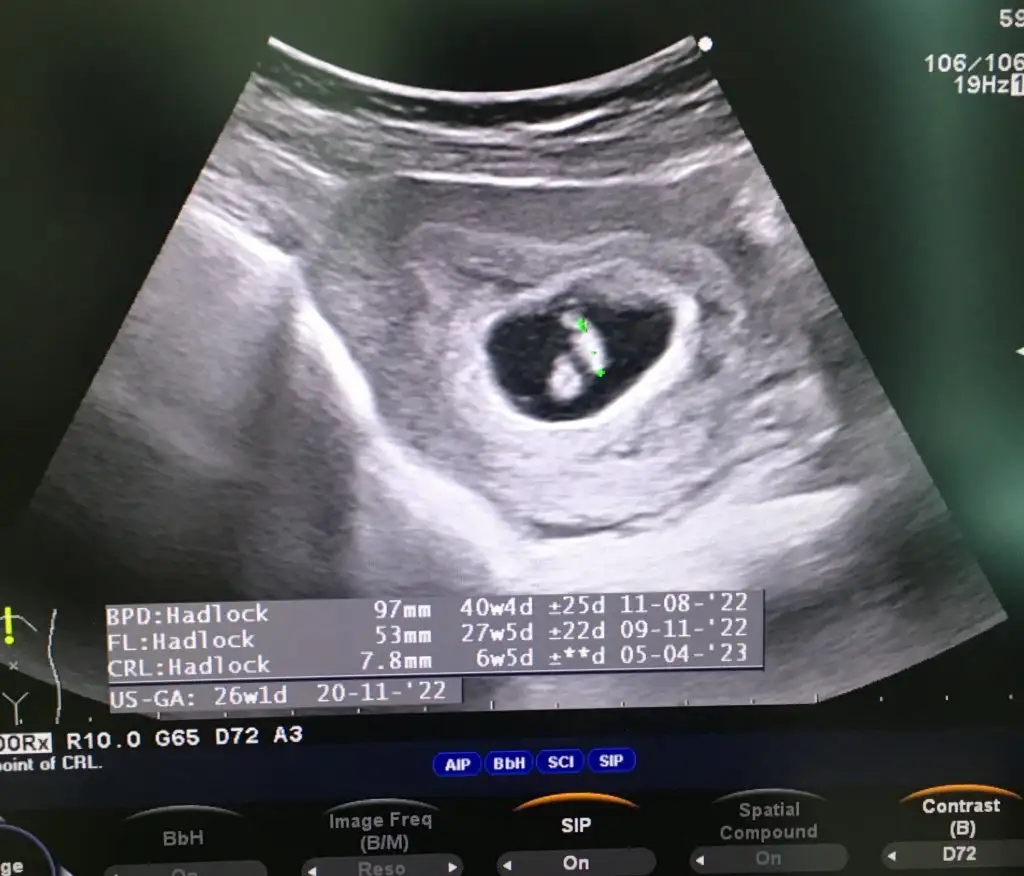

Kese uzunsa erkek yuvarlaksa kız mi ?

Bu bir kiz bebek.

Kızlar bı arkadaş keseye göre tahmin yapıyor ve hep tutuyormuş iki oğlunu da bu şekilde cok yeniyken bile tahmin etmiş...ogullarinda kesesi hep uzunmuş muz gibi...yuvarlak ve yuvarlağa yakın olanlar hep kızdır diyor..ve bayağı emin konusuyor..benimki şişman bı fasulye gibi oo kesin kız görürsün dedi...sizlerin keselerinin şekli nasıldı ve cinsiyet neydi konusalimmi 😊